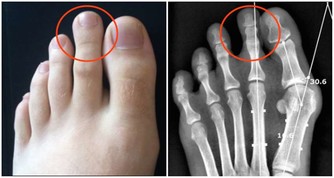

有人經常足跟痛,這就是腎虛。

您應多揉太溪穴,順著太溪穴把腎經的氣血引過去。

只要太溪穴被激活了,新鮮血液就會把淤血衝散吸收,自然就不痛了。